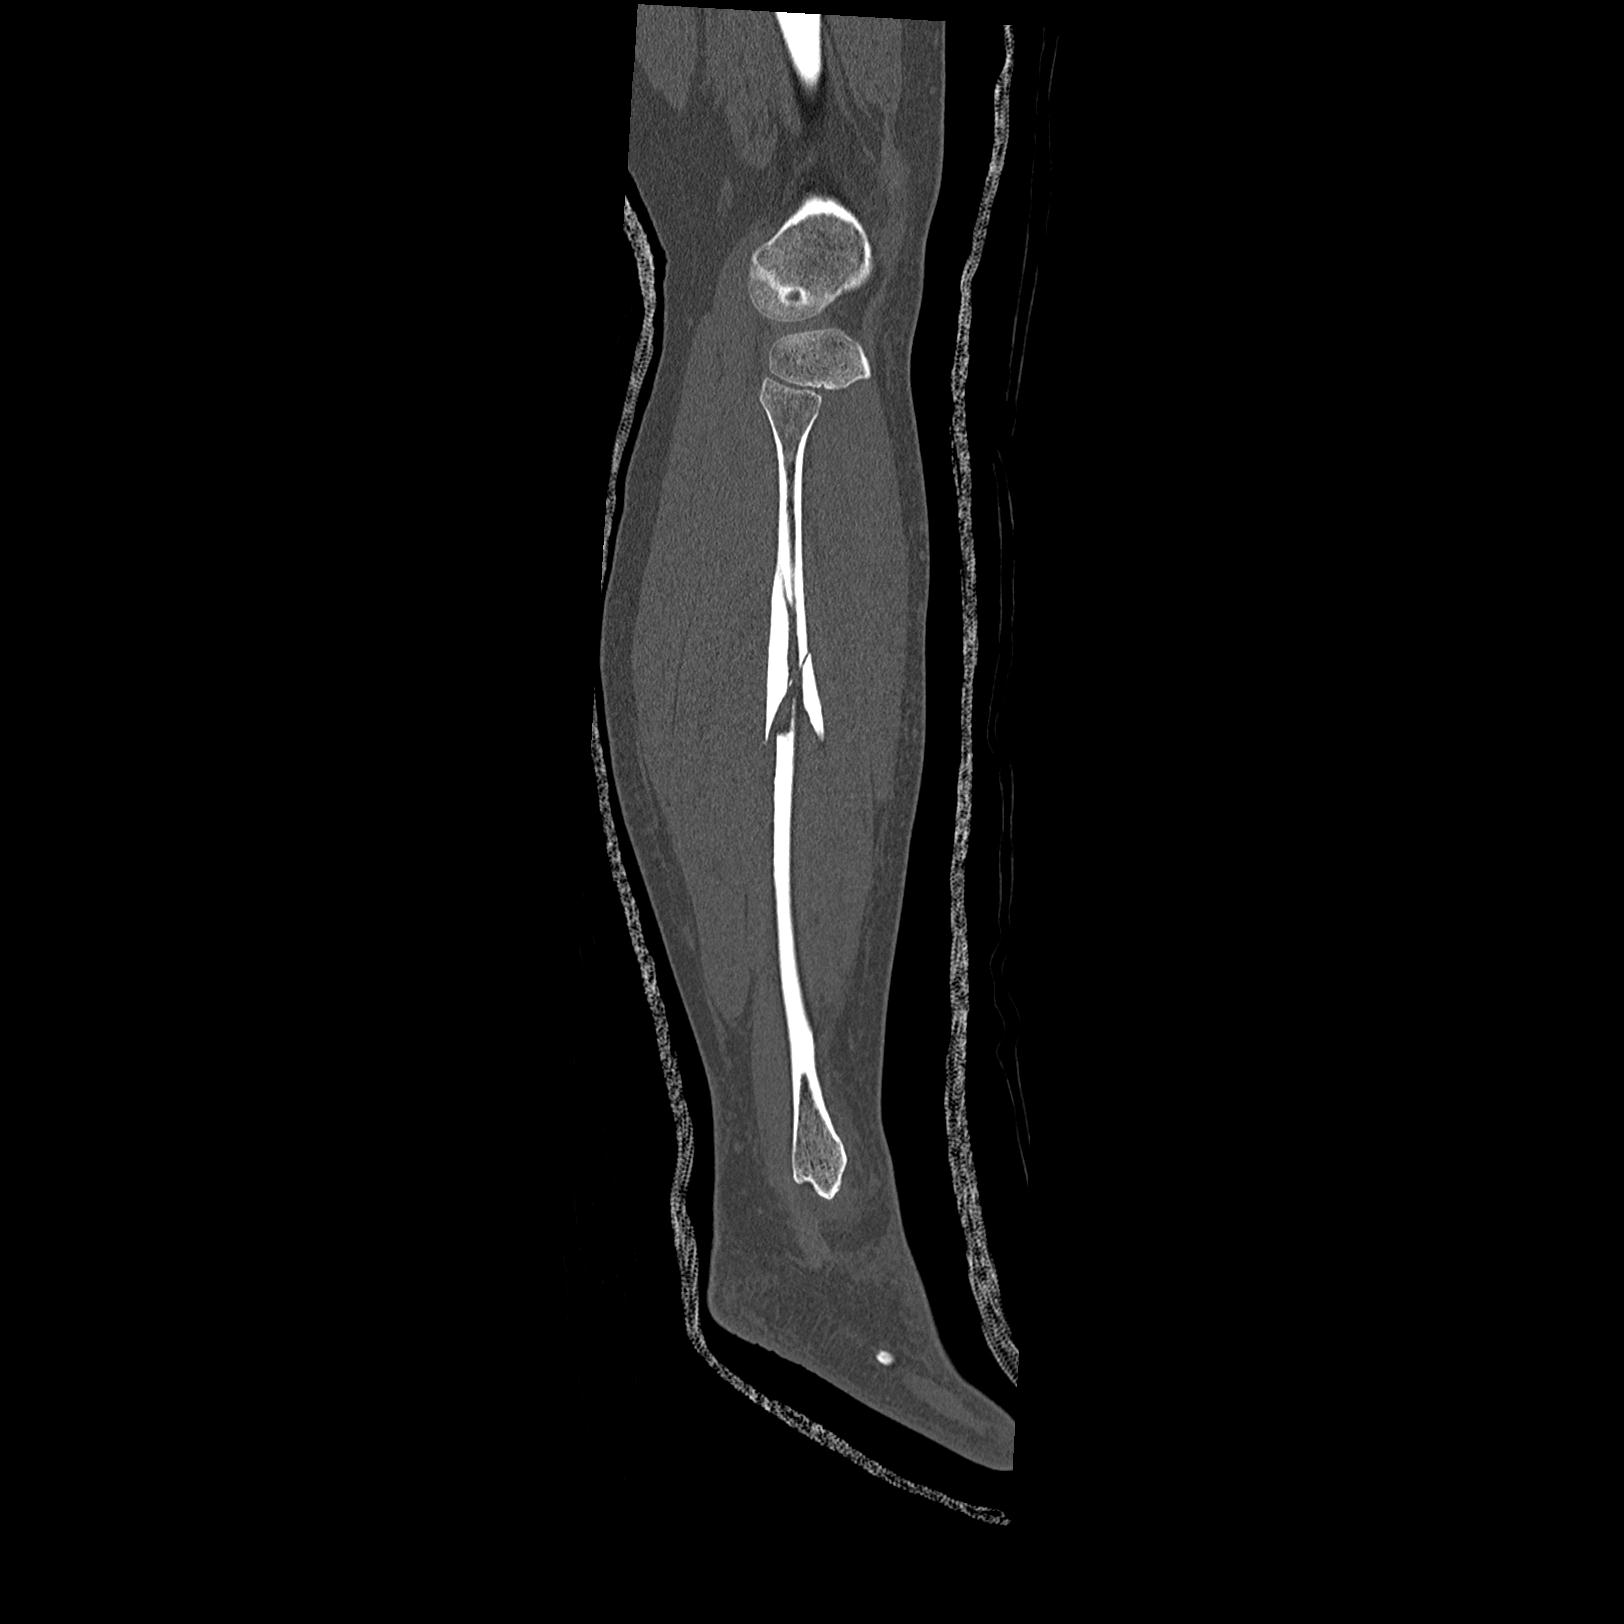

102803 1/12(キウスなし) 1/27 左下腿 4R 30歳女性 左脛骨軸内釘